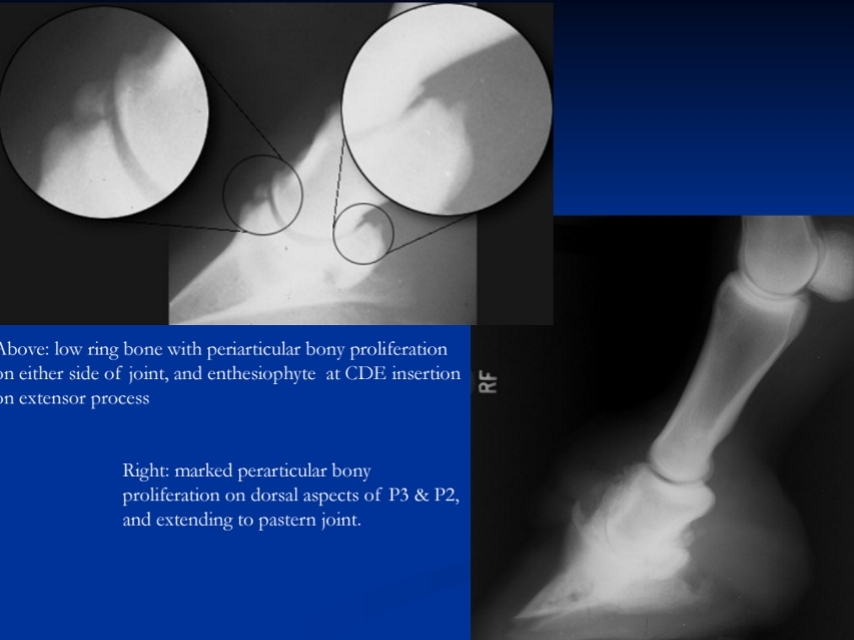

Low Ringbone

Et: Periarticular bony proliferation of DIP joint

Type 1: Chronic synovitis (bilateral)

Type 2: trauma (unilateral)

collateral ligament tear

Cs: Short, choppy bilateral gait, pain on flexion, weight shifting, bone proliferation, joint narrowing

Dt: Rads, perineural + intraarticular anesthesia response

Tx: Rest, NSAIDs, steroids + HA, arthrodesis, neurectomy

Standard arthritis treatments

High Ringbone

High ringbone OA= distal P1 & proximal P2 bony proliferation

Et: Pastern arthritis

Chronic synovitis or lig injury

bony proliferation, joint space narrowing, sclerosis/lysis, osteophytes

Cs: Chronic bilateral lameness w/ choppy gait, pain on flexion

Dt: rads

Tx: Correct foot balance, rest, IA steroids + HA, Arthrodesis (restore fxn)

Standard arthritis tx

Px: Guarded for performance